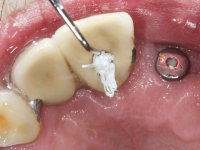

Foram feitas as extrações das raízes dos dentes 2.1 e 2.2 porque estavam a incomodar. Após 3 meses de cicatrização fez-se o exame imagiológico e estudo implantar para colocação do implante no local do 2.1.Foi colocado um implante de 4.1mm de diâmetro por 10mm de altura, colocado ao nível ósseo. Passados 2 meses após a cirurgia implantar, foi feita a segunda cirurgia para colocação de um parafuso de cicatrização. Foi feita a impressão ao implante com técnica de moldeira aberta com silicone de dupla viscosidade um mês após. No laboratório foi confecionada uma infraestrutura metálica para uma ponte de 2 elementos aparafusada ao implante. Esta infraestrutura apresentava 2 apoios palatinos para ajudar a estabilizar os dentes 1.1 e 2.3 a recuperar do traumatismo. Recuperados os dentes, os apoios poderiam ser retirados. Esta peça apresentava uma conexão interna ao implante com sistema anti-rotacional. A prova da infraestrutura foi feita em boca sendo o seu correto ajuste verificado com controle imagiológico. No revestimento da infraestrutura foi utilizada cerâmica de tonalidade coronária e gengival. Depois de verificada em boca e aprovada pelo paciente a ponte foi apertada definitivamente e o orifício de acesso obturado.